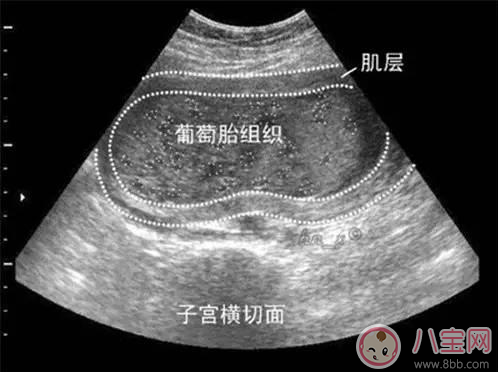

葡萄胎是由于絨毛膜滋養(yǎng)層細(xì)胞異常增生,絨毛發(fā)生水腫變形,呈無數(shù)個水泡相互連接,形似成串的葡萄,故名曰葡萄胎,又被稱為“水泡樣胎塊”。患有葡萄胎一旦確診后要刮宮處理。如果子宮不大,內(nèi)容物比較少,那么一次就可以刮干凈,對女性子宮的傷害也較小,但是如果內(nèi)容物比較多,有數(shù)不清的水泡,會轉(zhuǎn)移,一次很難刮干凈,那么需要兩次刮宮。

懷上了葡萄胎的婦女在妊娠初期和大多數(shù)正常懷孕的婦女都是一樣的,可以表現(xiàn)有惡心嘔吐等早孕反應(yīng),但是隨著妊娠月份的增加,“孕婦”開始出現(xiàn)了一些與正常妊娠不同的表現(xiàn)。比如會出現(xiàn)腹部疼痛及陰道不規(guī)則流血等癥狀,早孕反應(yīng)也通常比普通的妊娠婦女表現(xiàn)得更劇烈、更嚴(yán)重,甚至持續(xù)的時間更長;還有的婦女懷上葡萄胎后,腹部異常的增大,肚子看起來要比正常孕周大得多,有的人甚至誤以為自己是懷上的雙胞胎或者多胞胎,殊不知卻是空歡喜一場。